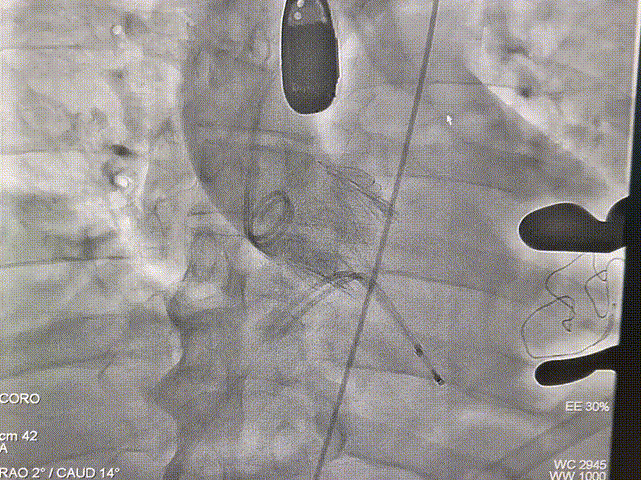

Case 1 患者为横位心重度返流,左锁骨下动脉-主动脉弓动脉瘤,降主动脉走形迂曲,胸-腹主动脉成角64度,左室流出道有凸出。经股入路成为禁忌,情况十分艰险。但在团队充分的术前准备和完整的手术策略支持下,成功经心尖植入一枚J-Valve介入瓣膜,完成了救治,患者获益良好。

Case 2 二叶瓣畸形病人,横位心,重度钙化伴返流,左室流出道重度钙化且伴有凸出,EF只有30%。安医大一附院TAVR团队凭借丰富的手术经验,默契配合,成功完成手术,术后造影显示,瓣膜位置立项,极轻微瓣周漏,冠脉血流通常。